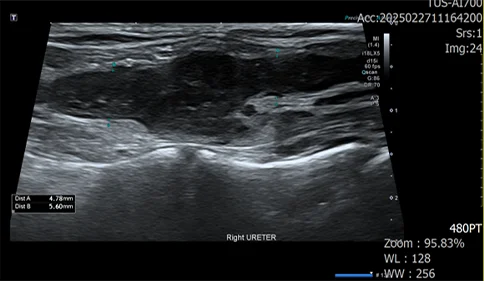

우측 신장 주변부 가스, 복수, 신장의 형태 변화, 신우의 확장, 요관 확장 확인

신우내 저류하는 액체 천자 진행, 점액성 농이 다수 확인

도말 상 세균 확인

정밀 검사 결과, 신장 주변 가스, 복수, 신장 파열이 확인되었습니다.

세균성 신우신염으로 인한 신장 파열이 발생, 그로 인한 이차적인 복막염으로 진행되는 상태입니다.